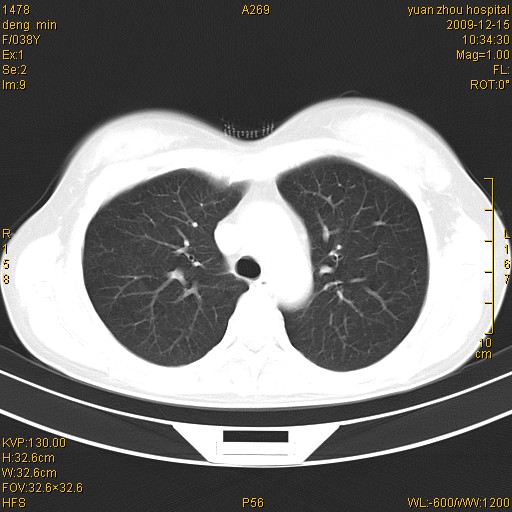

右肺中下叶、左肺上叶舌段及左肺下叶支气管扩张合并感染。